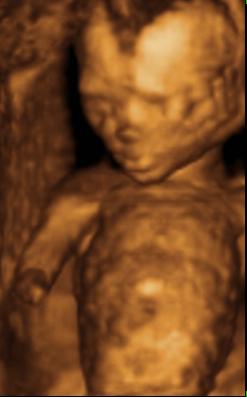

Ind, gyönyörű babád van

– köszi a képeket

Azt még megkérdezem, hogy ti most tulajdonképpen mennyi idősök vagytok? – a kép szerint 27hét+3nap, a vonalzód szerint pedig 26 hét.... – nagyobb a babád, mint kellene?